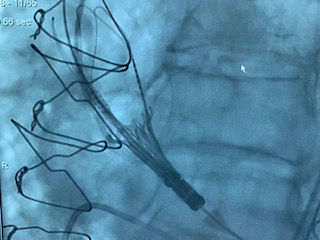

Alliberament d'una TAVI

Alliberament d'un TAV

Alliberament TAVI